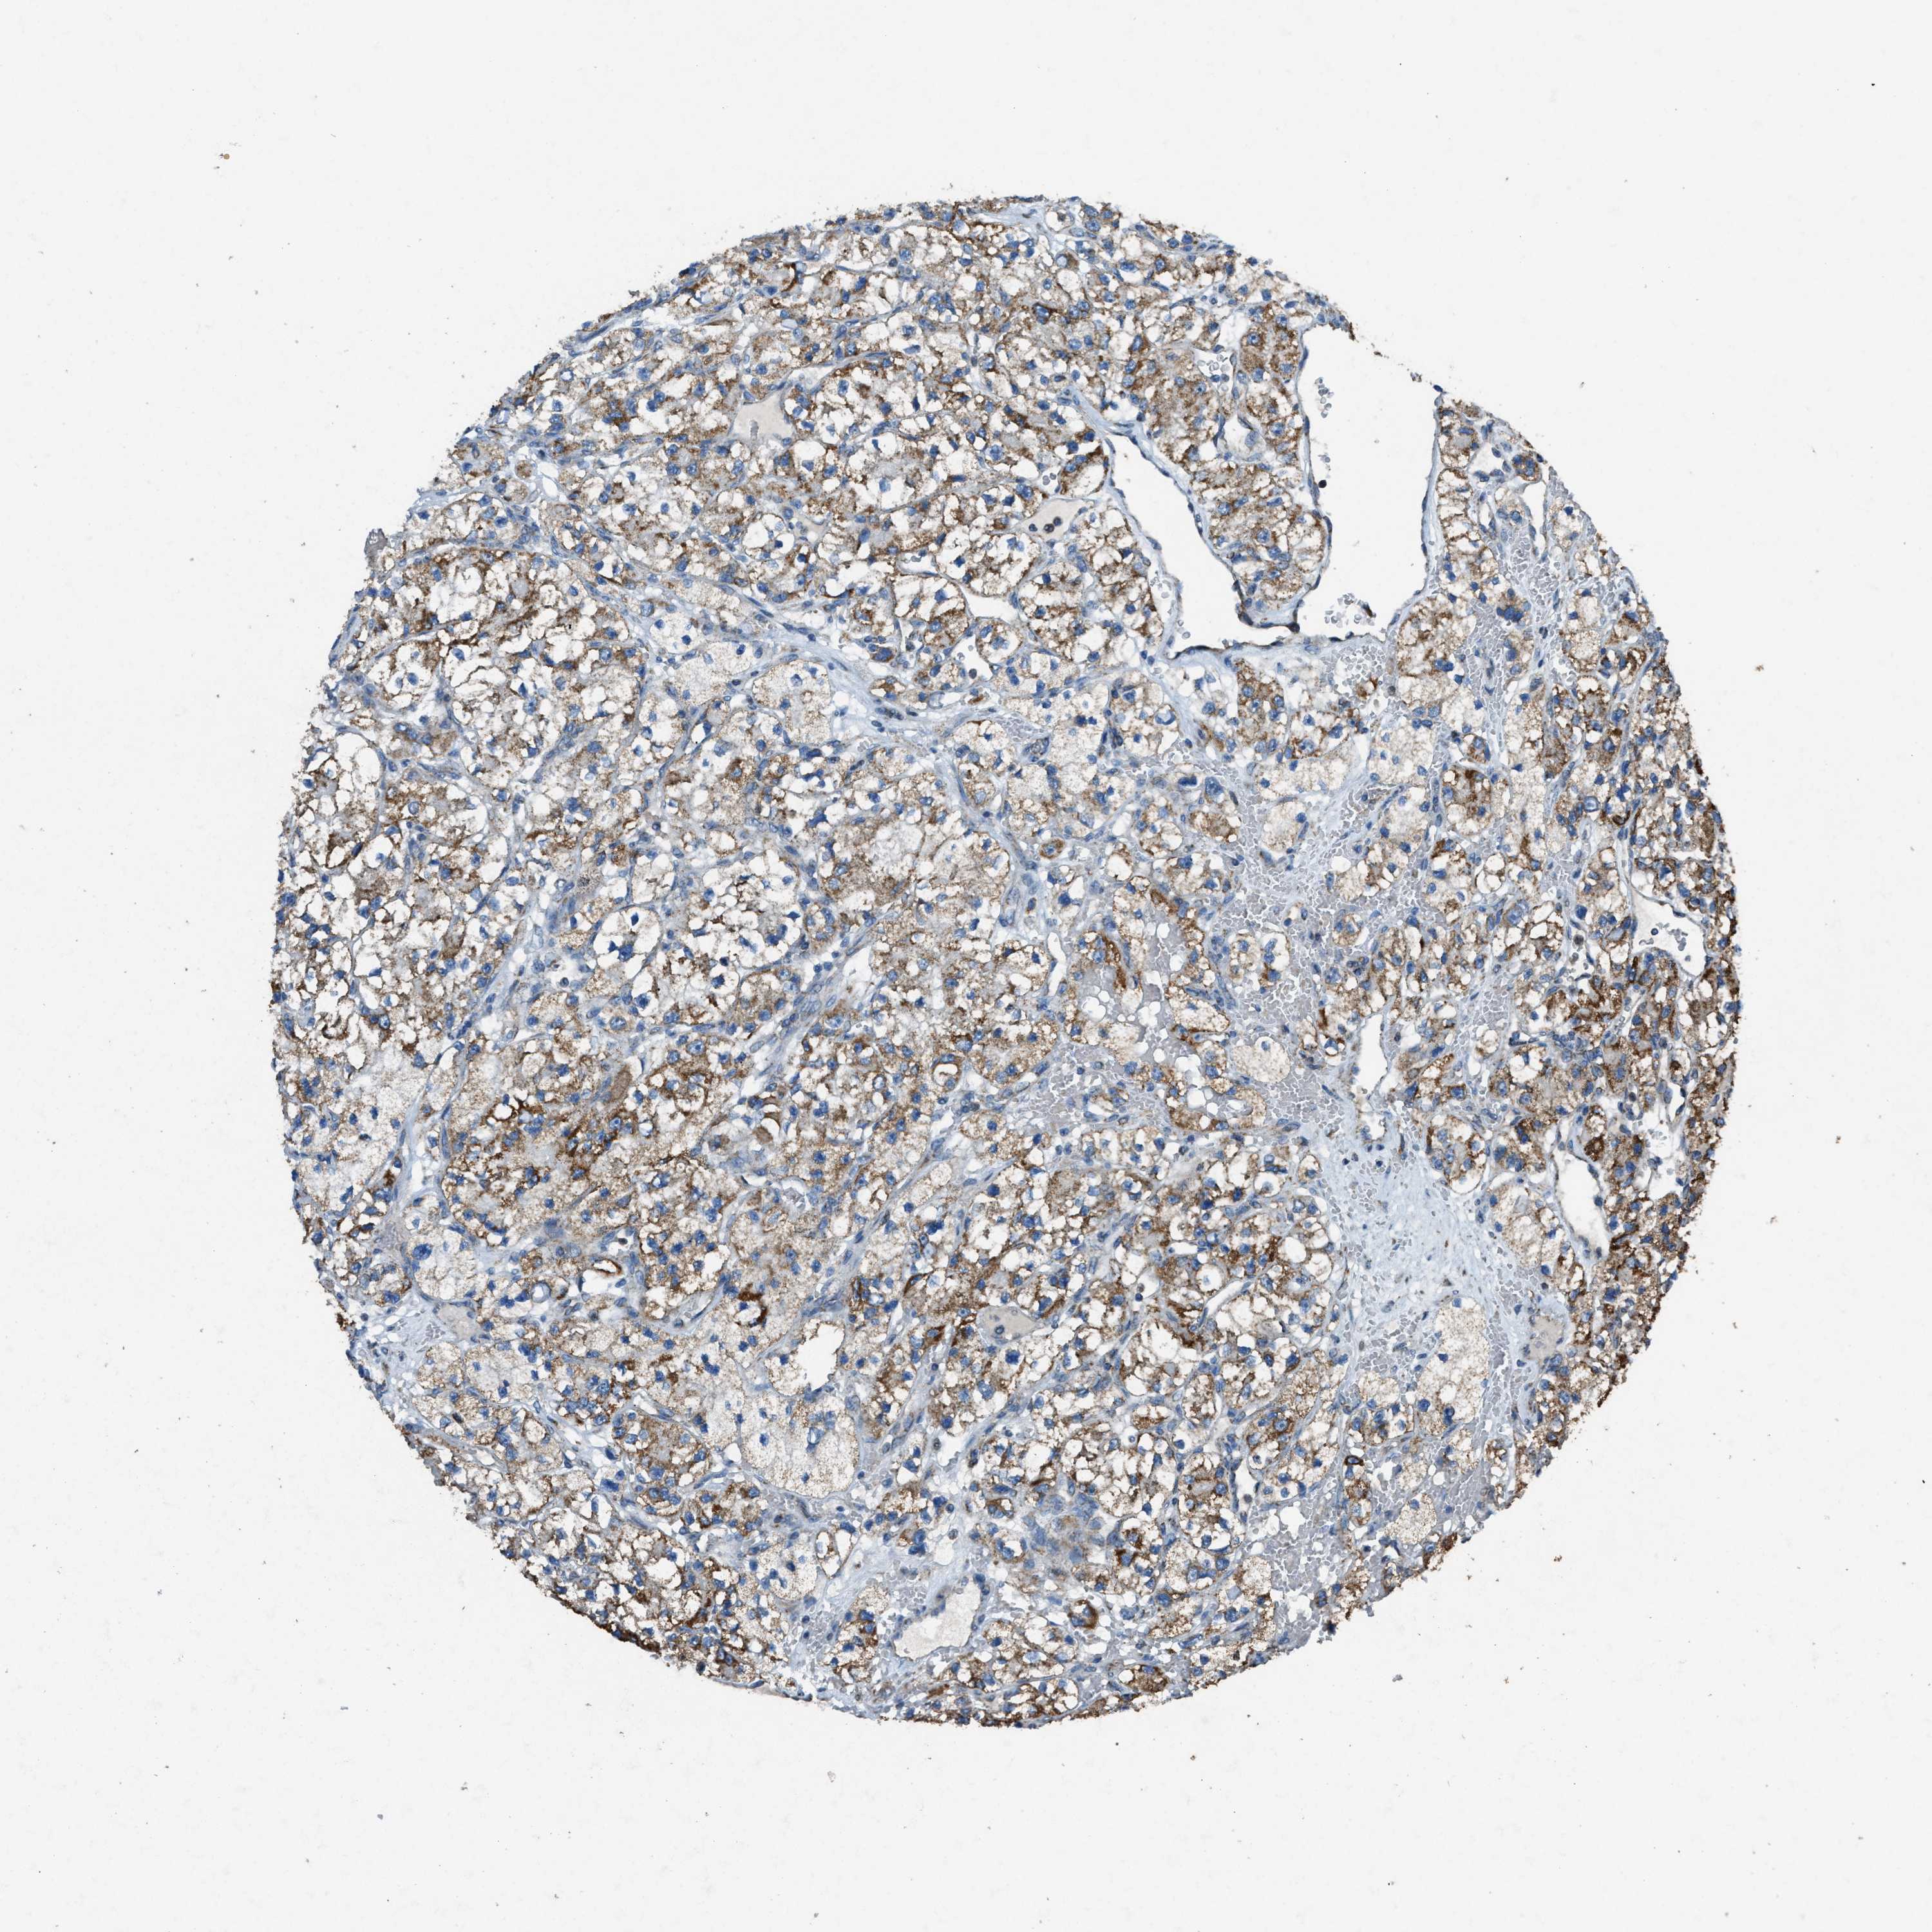

KIDNEY RENAL CLEAR CELL CARCINOMA (VALIDATION) - Interactive survival scatter ploti

The Survival Scatter plot shows the clinical status (i.e. dead or alive) for all individuals in the patient cohort, based on the same data that underlies the corresponding Kaplan-Meier plots. Patients that are alive at last time for follow-up are shown in blue and patients who have died during the study are shown in red.

The x-axis shows the expression levels (FPKM) of the investigated gene in the tumor tissue at the time of diagnosis. The y-axis shows the follow-up time after diagnosis (years). Both axes are complimented with kernel density curves demonstrating the data density over the axes. The top density plot shows the expression levels (FPKM) distribution among dead (red) and alive patients (blue). The right density plot shows the data density of the survived years of dead patients with high and low expression levels respectively, stratified using the cutoff indicated by the vertical dashed line through the Survival Scatter plot. This cutoff is automatically defined based on the FPKM cutoff that minimizes the p-score. The cutoff can be changed by dragging the vertical line or by entering a cutoff value in the square labeled "Current cut-off".

Under the Survival Scatter plot the p-score landscape (black curve; left axis) is shown together with dead median separation (red curve; right axis). Dead median separation is the difference in median mRNA expression between patients who have died with high and low expression, respectively. It is calculated as follows: median FPKM expression of dead patients with high expression - median FPKM expression of dead patients with low expression. This is intended to aid the user in visually exploring custom cutoffs and the associated p-scores and dead median separation.

Individual patient data is displayed and can be filtered by clicking on one or more of the category buttons on the top of the page. Categories describing expression level and patient information include: high, low, alive, dead, female, male and tumor stages. The scale of the x-axis can be toggled between linear and log-scale by clicking on the "x log" button. Mouse-over function shows TCGA ID, patient information and mRNA expression (FPKM) for each patient.

& Survival analysisi

Kaplan-Meier plots summarize results from analysis of correlation between mRNA expression level and patient survival. Patients were divided based on level of expression into one of the two groups "low" (under cut off) or "high" (over cut off). X-axis shows time for survival (years) and y-axis shows the probability of survival, where 1.0 corresponds to 100 percent.

SLC25A11 is not prognostic in Kidney Renal Clear Cell Carcinoma (validation)

Best expression cut offi

Based on the FPKM value of each gene, patients were classified into two groups and association between prognosis (survival) and gene expression (FPKM) was examined. The best expression cut-off refers the FPKM value that yields maximal difference with regard to survival between the two groups at the lowest log-rank P-value. Best expression cut-off was selected based on survival analysis .

When clicking on this number, the vertical dashed line indicating cut-off, the interactive survival plot, and the Kaplan-Meier curve will be adjusted to show results based on the best expression cut-off.

: 54.36

TCGA RNA samplesi

RNA-seq data is reported as average FPKM (number Fragments Per Kilobase of exon per Million reads), generated by the The Cancer Genome Atlas (TCGA) .

Normal distribution across the dataset is visualized with box plots, shown as median and 25th and 75th percentiles. Points are displayed as outliers if they are above or below 1.5 times the interquartile range. FPKM values of the individual samples are presented next to the box plot.

Average pTPM 65.8

Number of samples 100